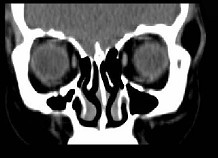

女,31岁,在左眶外上缘发现一包块,质软,余所见无明显异常。如图所示病灶应诊断为 ( ) 2YJB-16841.jpg 2YJB-16842.jpg 2YJB-16843.jpg 2YJB-16844.jpg

题型: 单选题 分类: 眼科学

• A.畸胎瘤

• B.错构瘤

• C.脂肪瘤

• D.表皮样囊肿

• E.淋巴管瘤